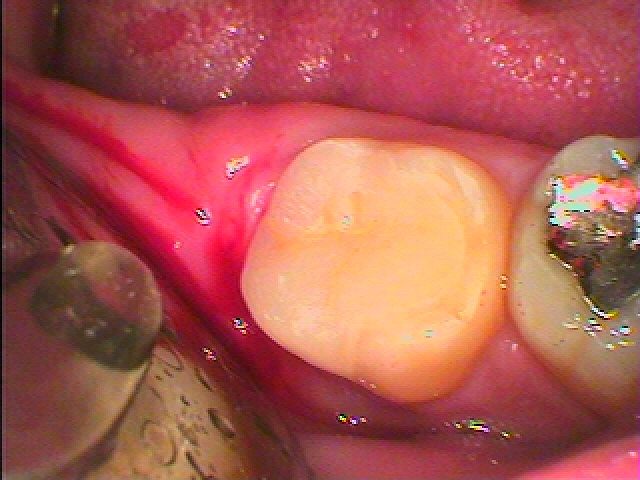

セレックセラミックにて審美的にもきれいに仕上げています